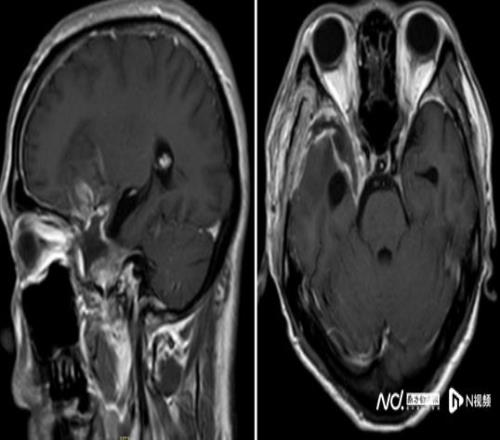

2025年10月起,他在跑步途中频繁在转弯处摔倒,偶尔还感觉一侧手脚乏力,起初并未放在心上。但随着摔跤次数不断增多,又无明显诱因地出现持续一周的头痛,他和家人终于警觉起来。同年11月中旬,陈叔家人带他在当地医院做了一次检查。MR结果如晴天霹雳:右额颞部蝶骨嵴占位病变,大小约5.5x6.6x5.8cm,考虑脑膜瘤。

鉴于肿瘤体积巨大、位置较深,考虑为右侧额颞蝶骨嵴内侧型巨大脑膜瘤,肿瘤突入垂体窝和斜坡,环绕颈内动脉及分支、视神经等重要结构,压迫脑干。手术难度是神经外科最复杂的手术之一,犹如刀尖上行走,且已出现进行性神经功能缺损症状:肢体乏力,视力受损,视物重影等,病情复杂、手术风险极高。